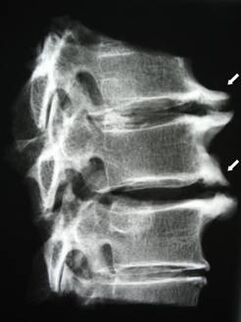

In the initial stages, osteochondrosis is detected using MRI.Later, the pathology can be diagnosed using radiographs.In radiographs of the cervical spine, a decrease in the distance between the vertebrae, pathological changes in the fascial joints and osteophytosis become visible.